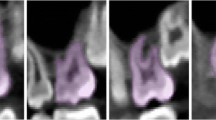

Landmarks were established for the tongue space (Fig. 1 and Table 1). The superior border of the tongue space was the palatal plane [anterior nasal spine (ANS) to posterior nasal spine (PNS)], parallel to the Frankfort horizontal plane (Fig. 2). This included the height of the palatal vault (HPV), which was the distance from the maxillary occlusal plane (tangential to the most distal points of the maxillary first molars) to the deepest point of the palate in the plane. The anterior border of the tongue space was the cingulum of the anterior teeth when they are in maximum intercuspation. The lateral border of the tongue space was the lingual side of the mandible (both right and left) all the way forward to the genial tubercle (GT). The inferior border of the tongue space was the hyoid bone to the genial tubercle and the anteroinferior point of the third cervical vertebra (C3) (Fig. 3). The posterior border of the tongue space was the left and right side gonion (Go) perpendicular to the Frankfort horizontal plane.

Posteriorly, the tongue space includes part of the airway, specifically part of the oropharynx. The oropharynx was divided into two areas: velopharynx and glossopharynx [22]. The velopharynx was defined from the horizontal level of the palatal plane to the horizontal level of the end of the uvula. The glossopharynx was defined from the horizontal level of the end of the uvula to the horizontal level of the C3 (the most anteroinferior point of the third cervical vertebra) [23]. The overall tongue space included the oral cavity and part of the airway superior to the hyoid bone to GT and anteroinferior point of C3 and inferior to the palatal plane (Fig. 1).

In this study, the landmarks circumscribing the areas of interest were carefully selected based on the anatomy of the tongue and airway (Fig. 1 and Table 1). Each of these landmarks is easily recognizable and by having a standardized protocol for capturing CBCT images, these landmarks should provide accurate and reproducible measurements. The overall tongue space has to reflect all the space that the tongue occupies during normal activities such as breathing, speech, swallowing, and mastication. Several of the chosen landmarks were hard tissue instead of soft tissue because the soft tissues are continuously moving or may move depending on the activities.

The superior border of the tongue space was the palatal plane [anterior nasal spine (ANS) to posterior nasal spine (PNS)]. This was chosen because there were lots of changes to the position of the soft palate. For example, on the onset of the swallowing reflex, the soft palate is being drawn upward [36]. Posteriorly, the tongue space reaches the gonion of the mandible, and part of the airway, specifically portions of the oropharynx, which can be divided into the velopharynx and glossopharynx. The oropharynx extends from the soft palate to the most anteroinferior part of the C3 and includes the base of the tongue [37]. The inferior landmarks include the genial tubercle, hyoid bone, and anterior, inferior of C3. The reason we chose the landmarks described above is that the floor of the mouth consists of the geniohyoid and mylohyoid muscle. The origin of the geniohyoid muscle is the inferior mental spine of the mandible, while the insertion is the hyoid bone. The origin of the mylohyoid muscle is the mylohyoid line of the mandible, and the insertion of the muscle is the body of the hyoid bone. The C3 was chosen, because the hyoid bone lies at the level of C3 [38]. Since the hyoid bone is the inferior border of the tongue space, we proposed the C3 is a good reference point for the posteroinferior portion of the tongue space.

Even though the T0 and T1 CBCT scans were taken using a standardized protocol, it is almost impossible to have identical positioning at different time points. Minor changes in head posture will change the airway, hence possibly changing the overall tongue space [30, 31]. This is clearly illustrated in Fig. 5, where the inter-rater measurements (A–C) show that the head posture of one patient was significantly different between the two scans. The T0 vs. T1 image differences exceeded the limits of agreement, but both raters scored this patient consistently (Fig. 5d–f).